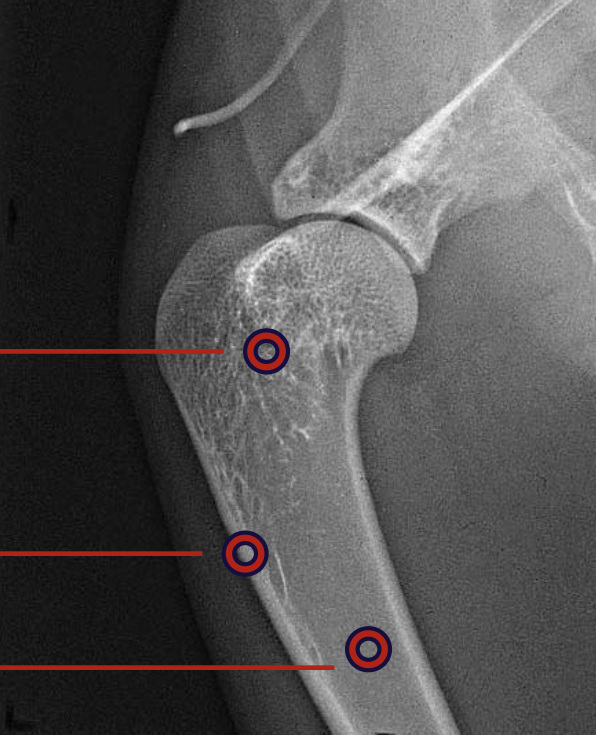

what is the top circling highlighting?

cancellous bone

what is the middle red circle highlighting?

cortex

what is the bottom red circle highlighting?

medulla